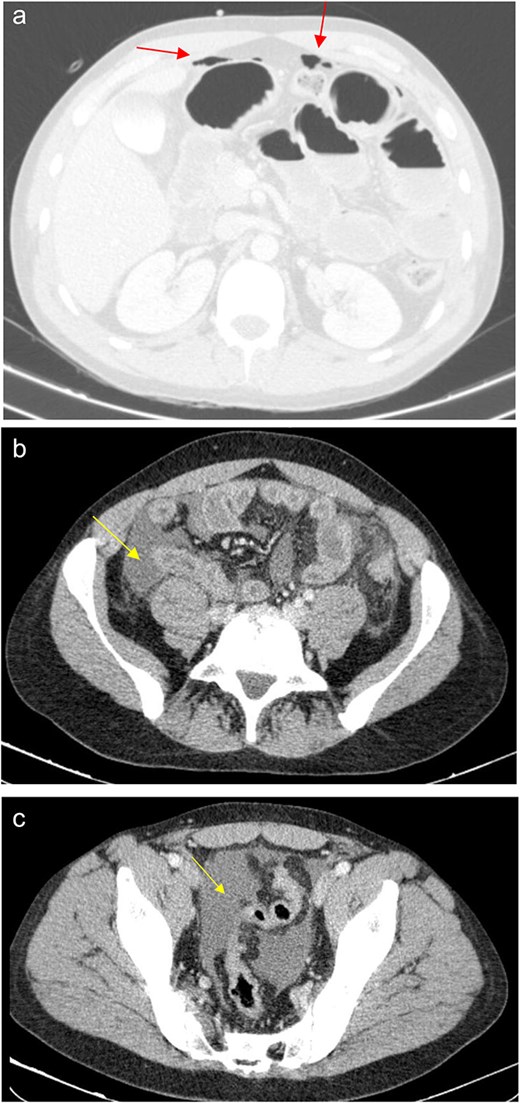

The patient presented at our Emergency Department with a sudden, diffuse, intense abdominal pain. Upon physical examination, the patient’s blood pressure was measured at 132/76 mmHg, heart rate of 103 bpm and a temperature of 39.4°C. The abdominal examination showed a rigid abdomen, with diffuse tenderness, suggesting an acute abdomen scenario. Laboratory tests revealed elevated inflammatory parameters. A abdominal and pelvic computed tomography scan revealed pneumoperitoneum and free fluid in the right iliac fossa and pelvis (Fig. 1). An exploratory laparotomy was proposed and the intraoperative findings included a sigmoid colon perforation with faecal peritonitis. They proceed with sigmoidectomy and temporary abdominal closure, planning for a reintervention to restore gastrointestinal continuity. This was done, after 48 h, through mechanical latero-lateral colo-colic anastomosis. The histopathological examination confirmed diverticulosis with perforation. The patient was subsequently transferred to the intensive care unit, for 5 days. Posteriorly, he developed severe left lumbar pain and hypertension unresponsive to medication. A CT scan revealed left kidney acute ischemia due to left renal artery thrombosis (Fig. 2). Broad-spectrum antibiotic therapy and anticoagulation, was initiated, after assessment by the Vascular Surgery and Urology teams. During his hospitalization, the patient experienced additional thrombotic events, such as occlusion of the left radial artery, and right lower lobar pulmonary embolism. A workup for prothrombotic conditions was conducted, including tests for thrombophilia, lupus, cardiolipins, antinuclear antibody, total protein test, and immunoglobulins, all of which were negative. An angiography of the abdominal aorta revealed arterial microaneurysms in the splanchnic territories: hepatic, perigastric and mesenteric arteries, suggesting polyarteritis nodosa (Fig. 3). Echocardiogram showed no abnormalities. The patient also underwent a study of the left shoulder due to repetitive pain complaints, with a suspected rupture of the rotator cuff. Electromyography excluded peripheral nerve damage. No other complications were reported. The patient was discharged on the 21st day after surgery, under anticoagulation therapy and steroids due to a suspected diagnosis of polyarteritis nodosa. Twenty-seven days after surgical intervention, the patient returned to the ED, presenting with abdominal pain in the lower quadrants and nausea. He was hemodynamically stable with abdominal pain and tenderness on the left flank and iliac fossa. Laboratory tests revealed leukocytosis and hyperlactacidemia. The CT scan reported free fluid, free gas bubbles adjacent to the sigmoid which had a concentric circular thickening of the wall, just distal to the previous anastomosis (Fig. 4). An exploratory laparotomy was performed, during which a large hematoma on the wall of the left colon was identified, with no apparent signs of perforation. A peritoneal lavage, drainage, and a derivative ileostomy were carried out. During the post-operative period the patient maintained a small volume of purulent discharge through the abdominal drain, with no abdominal tenderness. A reevaluation CT scan was performed, highlighting a regression of the hematoma of the colonic wall but raised suspicion of a low output fistula near the anastomosis. Since the patient maintained hemodynamic and analytical stability, he was discharged from the hospital with home care, including an abdominal drain, parenteral nutrition, empirical antibiotic therapy, and gradual reduction in the steroid dosage. The patient was referred to the ED, on Day 6, due to enteric drainage. An enterocutaneous fistula was diagnosed, and he was readmitted. He received 12 days of full-dose parenteral nutrition, which reduced the fistula output and improved his clinical and analytical status. Due to residual drainage volume and an analytical and imagiologic improvement, the drain was removed, and the patient was discharged, tolerating an oral diet, and with a functioning ileostomy.

(a) Pneumoperitoneum (arrowheads). (b) Free fluid in the right iliac fossa (arrowhead). (c) Free fluid in the pelvis (arrowhead).